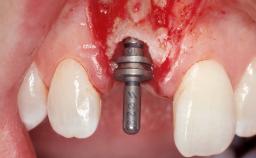

Late Flapless Placement of an Implant in a Maxillary Left Central Incisor Site

A 39-year-old male patient presented with a chief complaint of discomfort and gingival discoloration around his maxillary left central incisor. He was in good general health and was a non-smoker. His past dental history was significant because of the traumatic fracture of tooth 21 in a sporting accident at age 13. Initial dental treatment included endodontic therapy and a full-coverage restoration. The patient became symptomatic 5 years later, when structural failure of the tooth resulted in the dislodgment of the crown. Endodontic retreatment, apical surgery, and post-and-core restoration were performed.

Bone Augmentation Horizontal|Staged

Augmentation Materials Xenogenous|Membrane

Soft Tissue Grafting Simultaneous

Bone Volume Deficient horizontally, requiring prior grafting